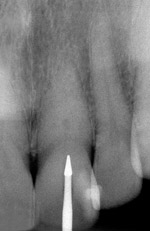

Fig. 21 Preoperative condition with normal calcification of tooth No. 8 and advanced calcific degeneration of the pulp of tooth No. 9.

Figure 21

Fig. 22 Radiograph with initial penetration of surgical length friction grip conical carbide bur. A slight redirection of the bur is indicated.

Figure 22

Fig. 23 Radiograph of deeper endo-exploration with the latch grip version of the conical carbide bur. Position confirmed as accurate.

Figure 23

Fig. 24 Shortly after Figure 23 radiograph was taken, the ideal angle of intersection of the residual pulp nicely directs the file into the calcified pulp chamber

Figure 24